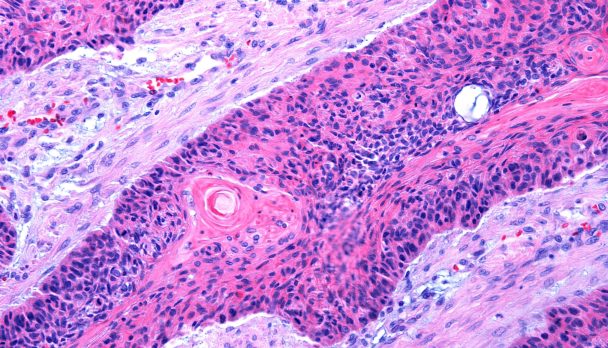

Not only are immunosuppressed people at increased risk of developing skin cancer, new research shows the skin cancer they get is more likely to be aggressive and multifocal.According to the retrospective study of a cohort of almost 800 patients who had been treated for cutaneous SCC of the head and neck at a US tertiary cancer care centre, immunosuppression was found to be independently associated with a worse outcome.

The latest updated version of the clinical practice guidelines for keratinocyte cancer are now available and worth checking out, especially if you do a lot of skin work.Keratinocyte cancer is the new way to talk about non-melanoma skin cancer and basically refers to basal cell carcinomas and squamous cell carcinomas.The new guidelines, which were developed by an Australian ‘non-remunerated working group’, incorporate a number of recent developments in the non-surgical treatment of these cancers. They provide suitable options for treating more advanced and metastatic cancers, and give guidance on how to manage patients who are believed to be at greater risk of developing these cancers, eg those who are on immunosuppression therapy.